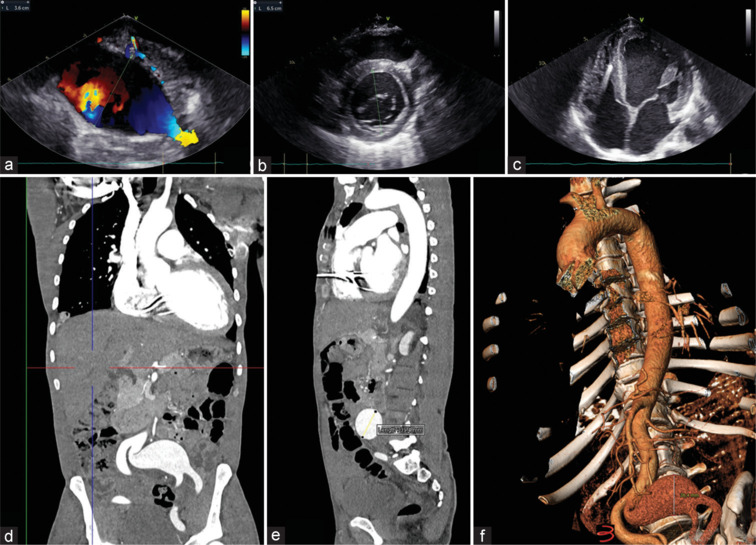

粪圆线虫是一种俗称蛔虫的线虫。人类是这种寄生虫的主要宿主,当裸露的皮肤暴露在被污染的土壤中时就会被感染。一旦进入人类宿主的皮肤,幼虫就会通过血液迁移到心脏,然后进入肺部的肺泡,最后进入气管,在那里幼虫被咳嗽和吞咽。临床上,这种感染可能无症状,也可能表现为急性或慢性胃肠道不适、过度感染综合征或累及不同器官的弥散性疾病。心肌炎和血管炎已被描述。在这里,我们描述的病例患者有扩张性心肌病和新发现的常见髂动脉瘤,其类圆线虫感染可能是这两种情况的结合特征。

Strongyloides stercoralis is a nematode commonly known as roundworm. Humans are the primary host for the parasite and are infected when bare skin is exposed to contaminated soil. Once in the skin of the human host, the larvae migrate to the heart through the blood and then to the alveoli of the lungs, subsequently ending up in the trachea where the larvae are coughed up and swallowed. Clinically, this infection may be asymptomatic as well as present as an acute or chronic gastrointestinal discomfort, hyperinfection syndrome, or disseminated disease with the involvement of different organs. Myocarditis and vasculitis have been described. Here, we describe the case of a patient with a history of dilated cardiomyopathy and the novel finding of common iliac artery aneurysm in whose Strongyloides infection might be the trait d'union of these two conditions.